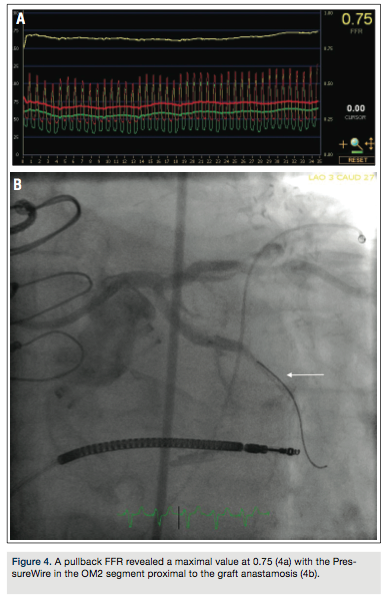

Coronary angiography revealed severe native disease involving a mid left circumflex artery 70-

80% stenosis at the second and third obtuse marginal (OM) branch bifurcation, with competitive flow noted in the distal OM2 branch (Figure 1). Selective graft angiography of the left internal mammary artery (LIMA) to the mid left anterior descending artery demonstrated a patent jump graft from LIMA to OM2 with a distal anastamotic 60-70% stenosis (Figure 2). Due to concern for the adequacy of perfusion of the OM2 segment via the native circulation or the jump graft, a strategy to measure the fractional flow reserve (FFR) in the distal OM2 branch was pursued. After maximal hyperemia using intravenous adenosine infusion at 180 mcg/kg/min, maximal FFR was calculated at 0.80 (Figure 3a) with a PressureWire (St. Jude